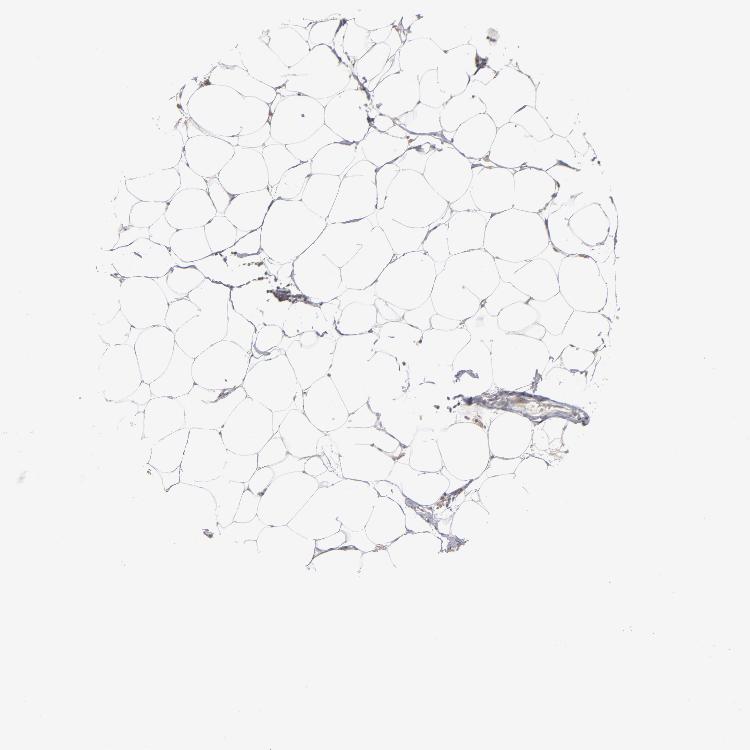

SOFT TISSUE 1 - Antibody stainingi

Antibody staining in the annotated cell types in the current human tissue is reported as not detected, low, medium, or high, based on conventional immunohistochemistry profiling in selected tissues. This score is based on the combination of the staining intensity and fraction of stained cells.

Each image is clickable and will lead to virtual microscopy that enables deeper exploration of all samples and also displays staining intensity scores, fraction scores and subcellular localization as well as patient and tissue information for each sample.

Antibody HPA002913

Fibroblasts Medium